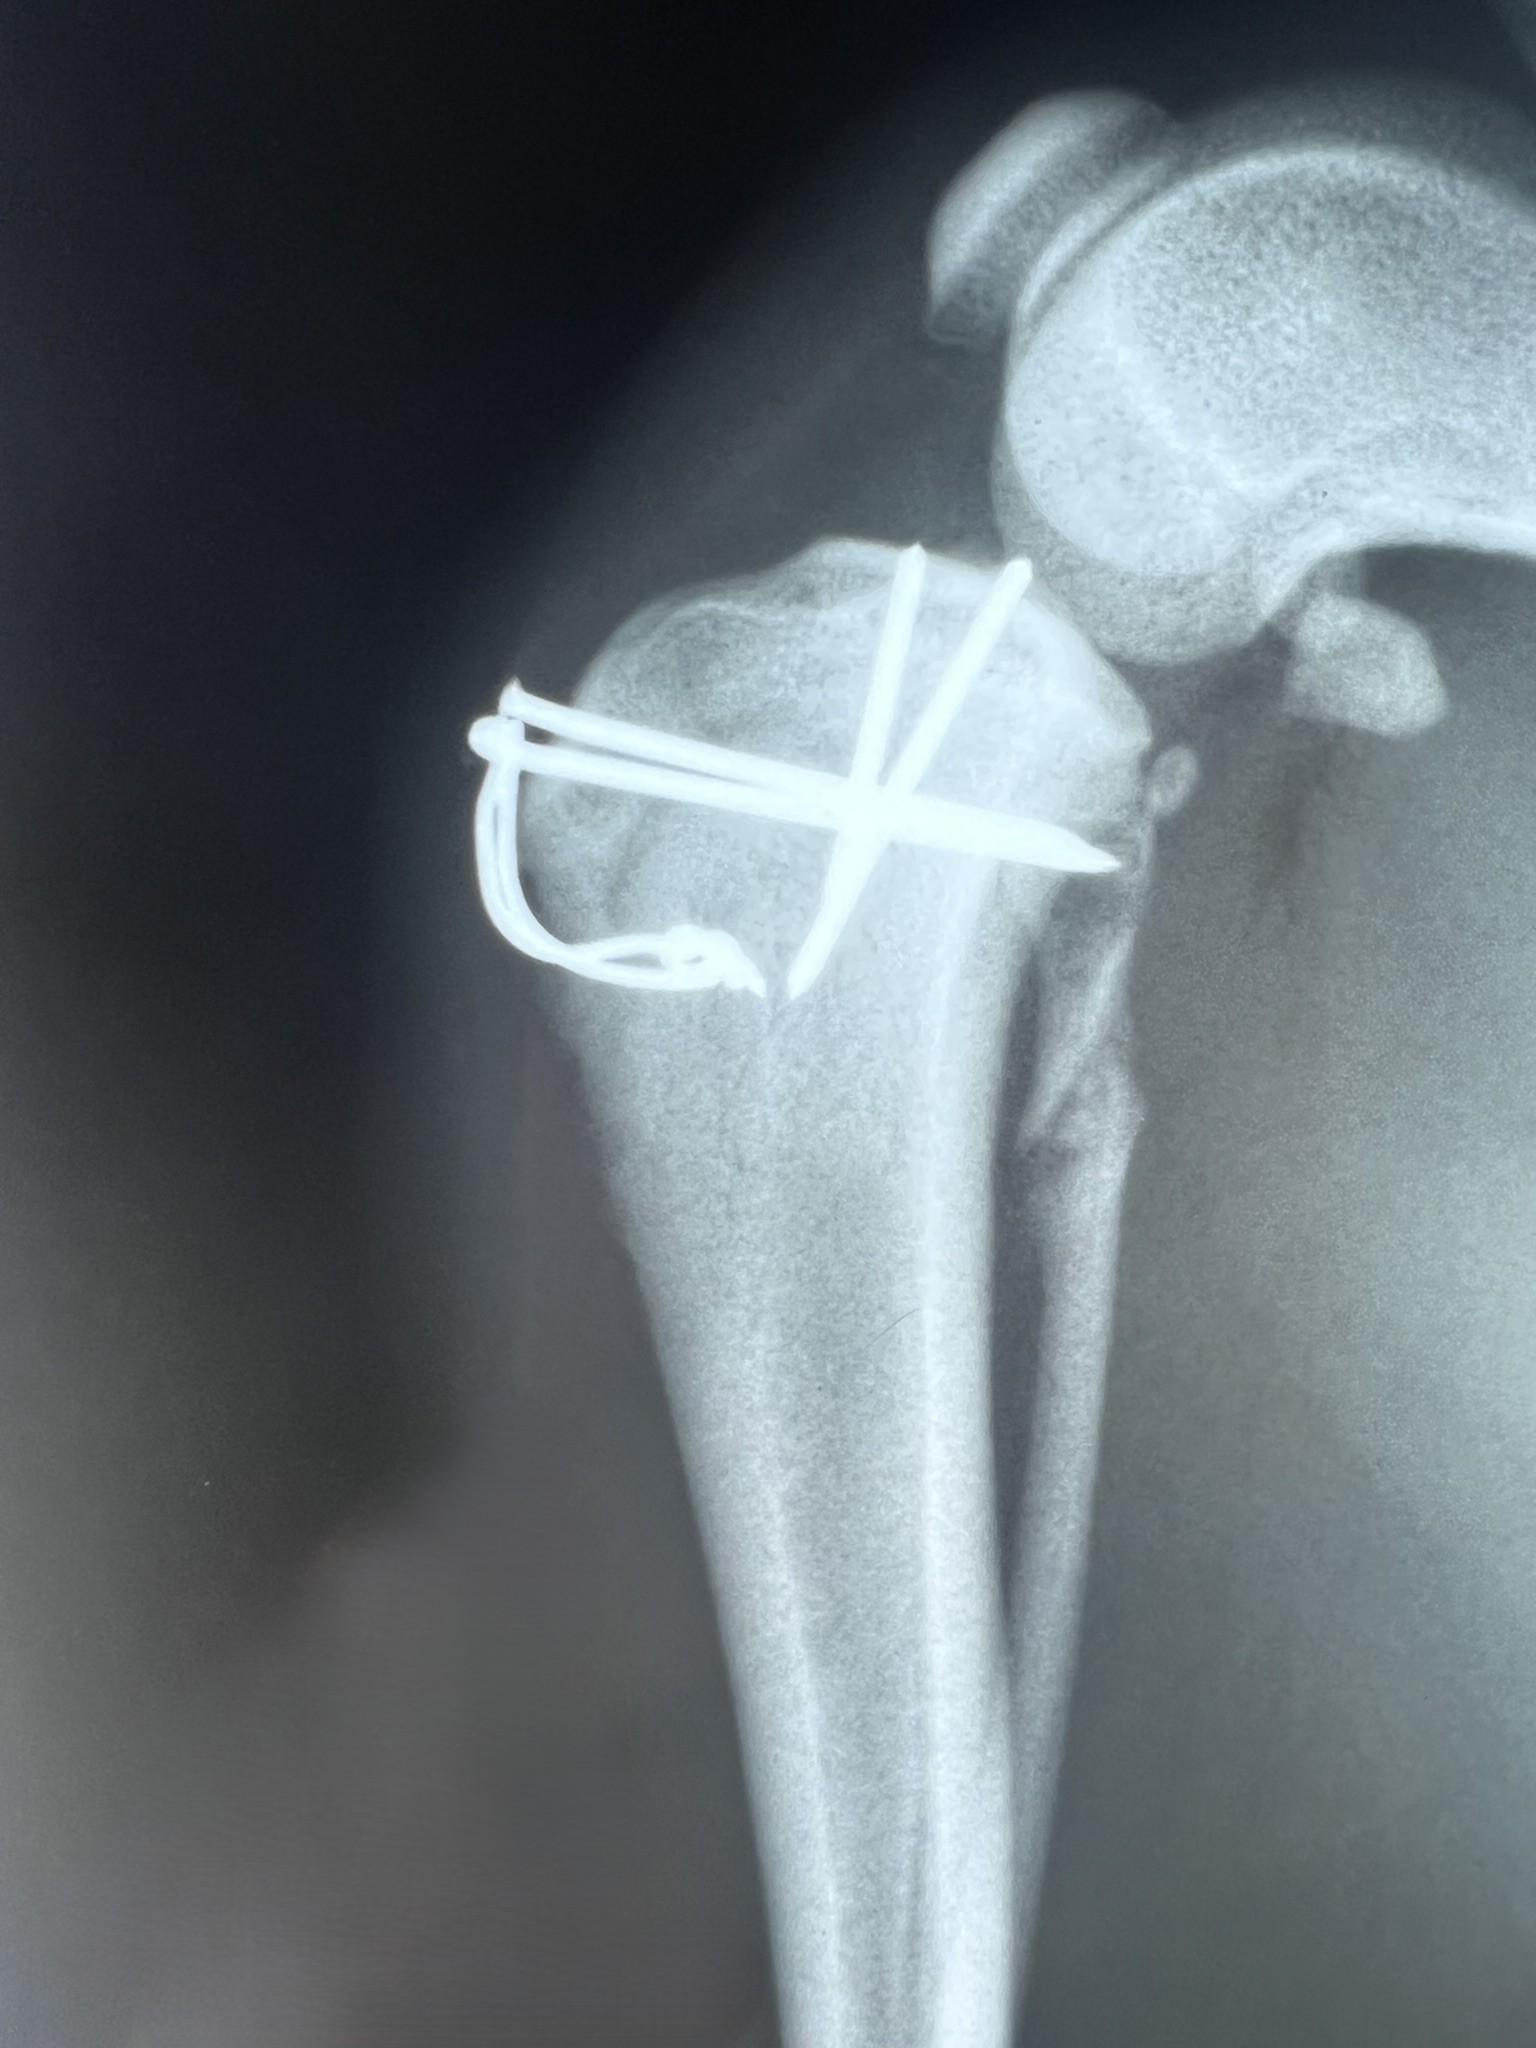

Screws, Pins and Wire

When fragments are very small or near the joint, we are limited to using small implants. These are relatively weak and more prone to failure or loosening. Often a bandage will be used post-operatively to help protect these repairs.

Articular humeral fracture in a puppy

Growth Plate tibial fracture in a puppy